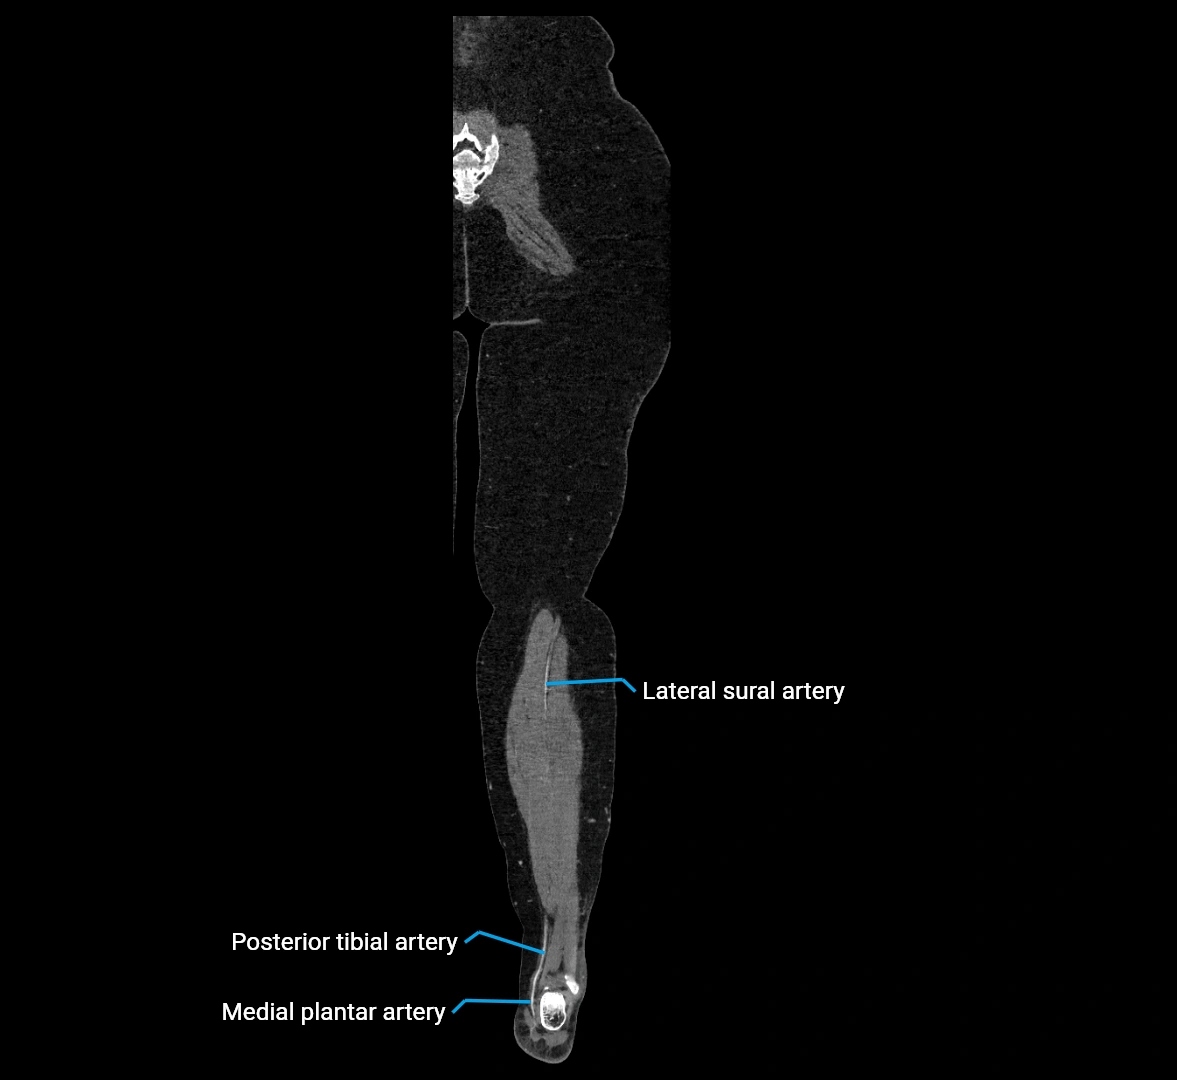

Contrast-enhanced CT (CTA):

• Gold standard for abdominal aortic imaging

• Provides excellent detail of lumen, wall, aneurysm, thrombus, and branch vessels

• Multiplanar and 3D reconstructions help in aneurysm measurement, stent graft planning, and dissection evaluation